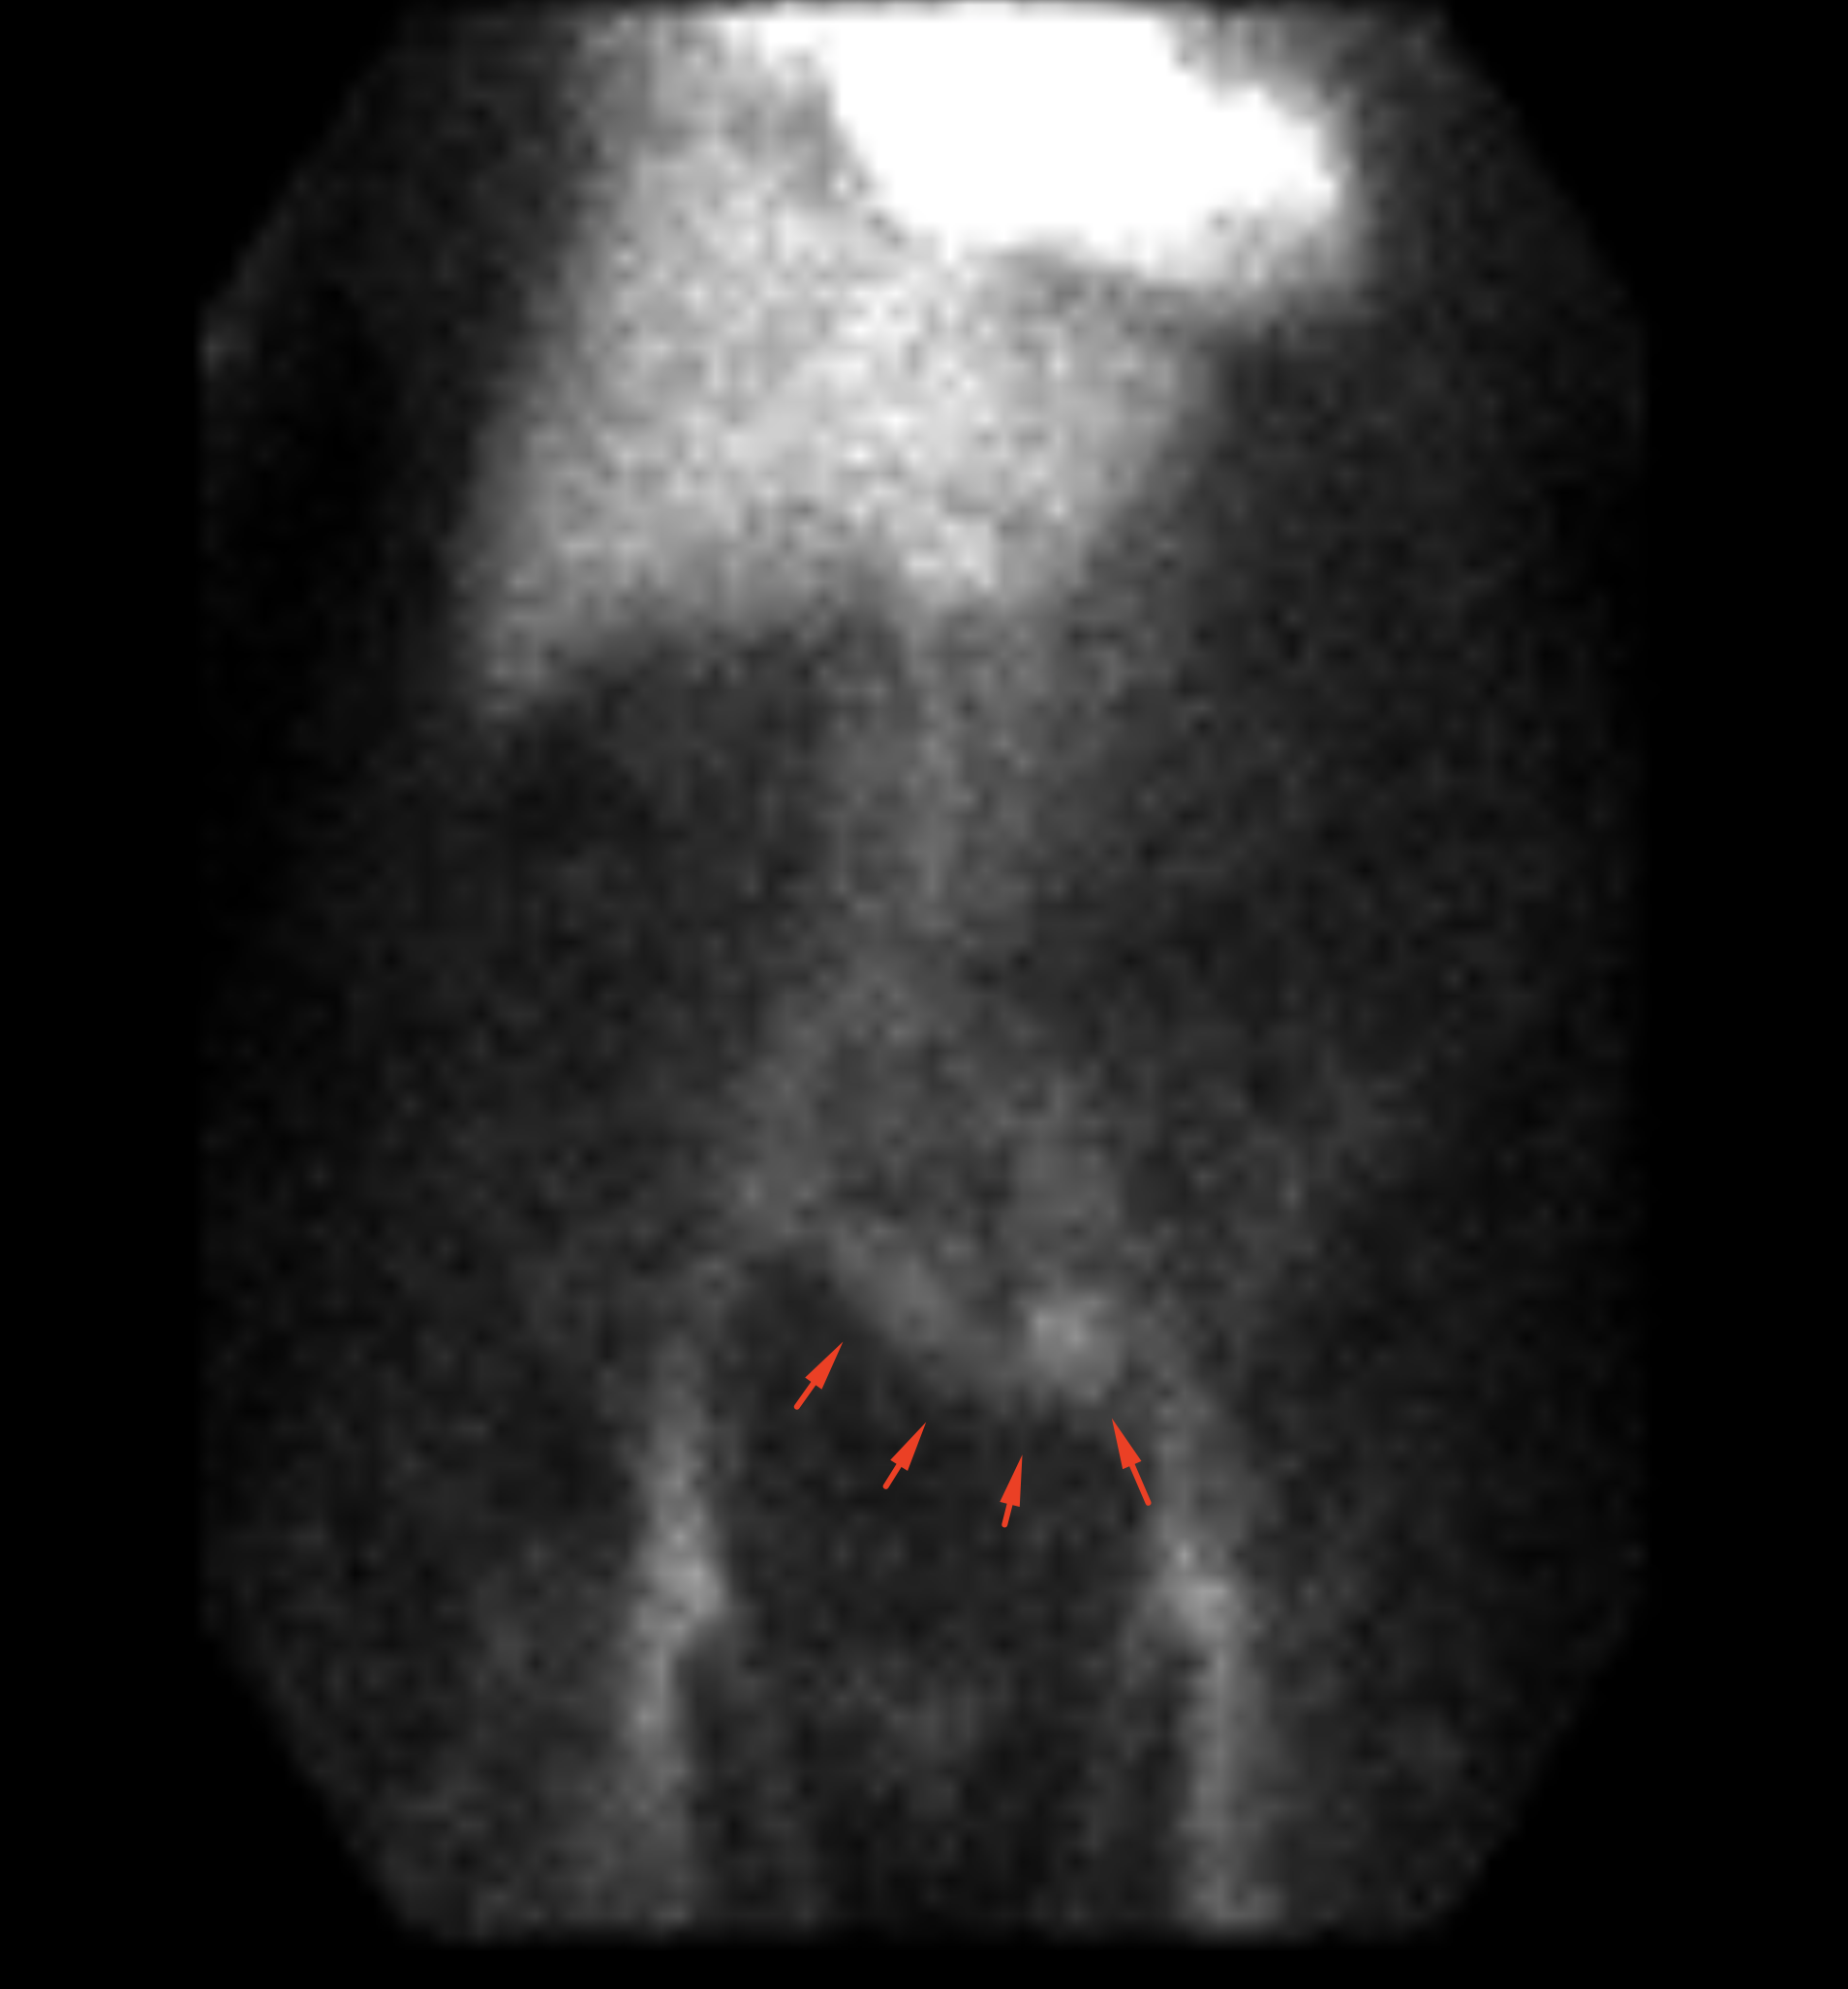

Age: 93

Sex: Female

Indication: Rectal bleeding

Radiotracer: Tc99m labeled RBCs

Sample ReportPositive for active GI bleeding with origin favored to be within the sigmoid colon.